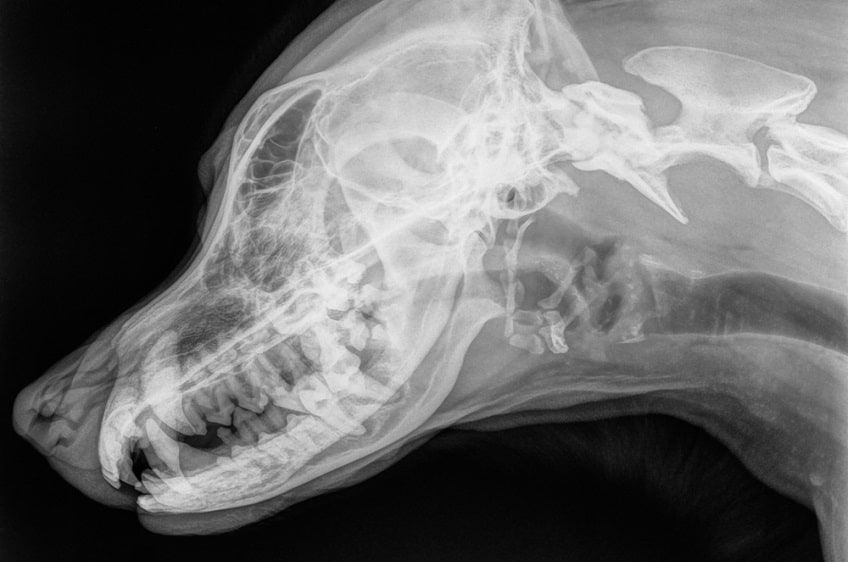

Diagnostyka chorób dziąseł u psów

Szybkie podjęcie leczenia zapalenia dziąseł może prowadzić do całkowitego wyleczenia choroby. Jednak gdy procesem zapalnym objęte zostaną także inne struktury przyzębia, dojść może do nieodwracalnych uszkodzeń. Dlatego przypadku zauważenia u psa pierwszych oznak zapalenia jamy ustnej, opiekun powinien jak najszybciej zabrać pupila do lekarza weterynarii.

Specjalista przeprowadzi szczegółowe badanie stomatologiczne – obejrzy dokładnie stan jamy ustnej czworonoga i oceni stopień zaawansowania choroby. Może też zlecić wykonanie RTG, dzięki któremu sprawdzi, czy choroba nie objęła zębów i kości zwierzaka. W przypadku zapalenia dziąseł ważne jest także badanie krwi, które pozwoli wykluczyć bakteryjne zakażenia innych narządów czworonoga.

rtg zębów u psa-min.jpg

fot. Shutterstock